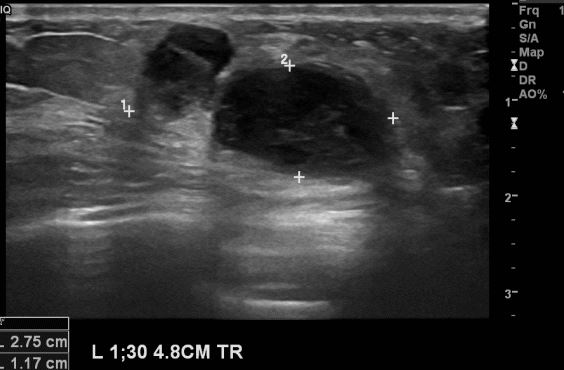

상기환자 좌측에 만져지는 멍울과 통증으로 내원하신 30대 여성분으로 본원 초음파

시행후   좌측 1시30분 방향에서 8cm 떨어진거리의 만져지는 멍울 조직검사 시행하여

좌측 침윤성 유관암 진단 되었습니다.